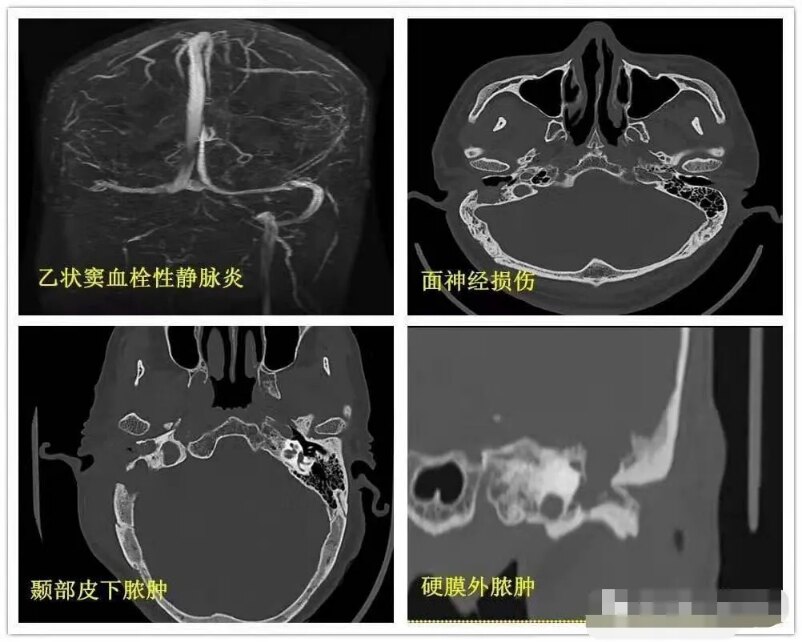

中耳炎ct